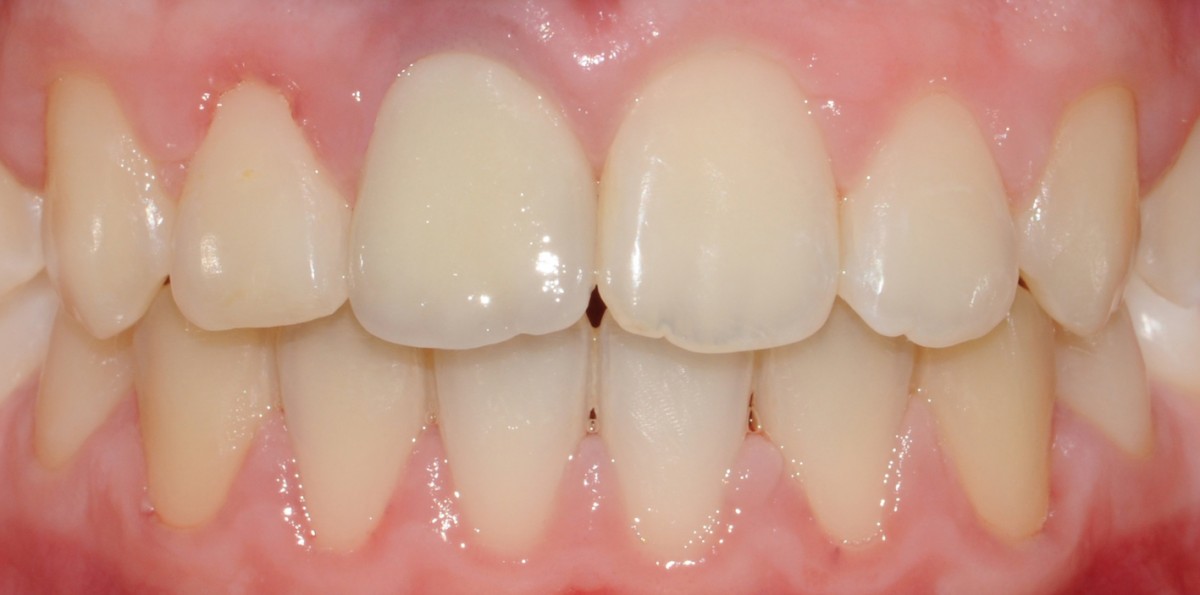

The case of a 13-year-old patient is presented, who was subjected to a single tooth den- to-osseous osteotomy for the treatment of an ankylosed and infraoccluded max- illary right central incisor.

Short term evaluation re- vealed a good soft tissue healing. After 6 months, there was no evidence of relapse in the tooth position.